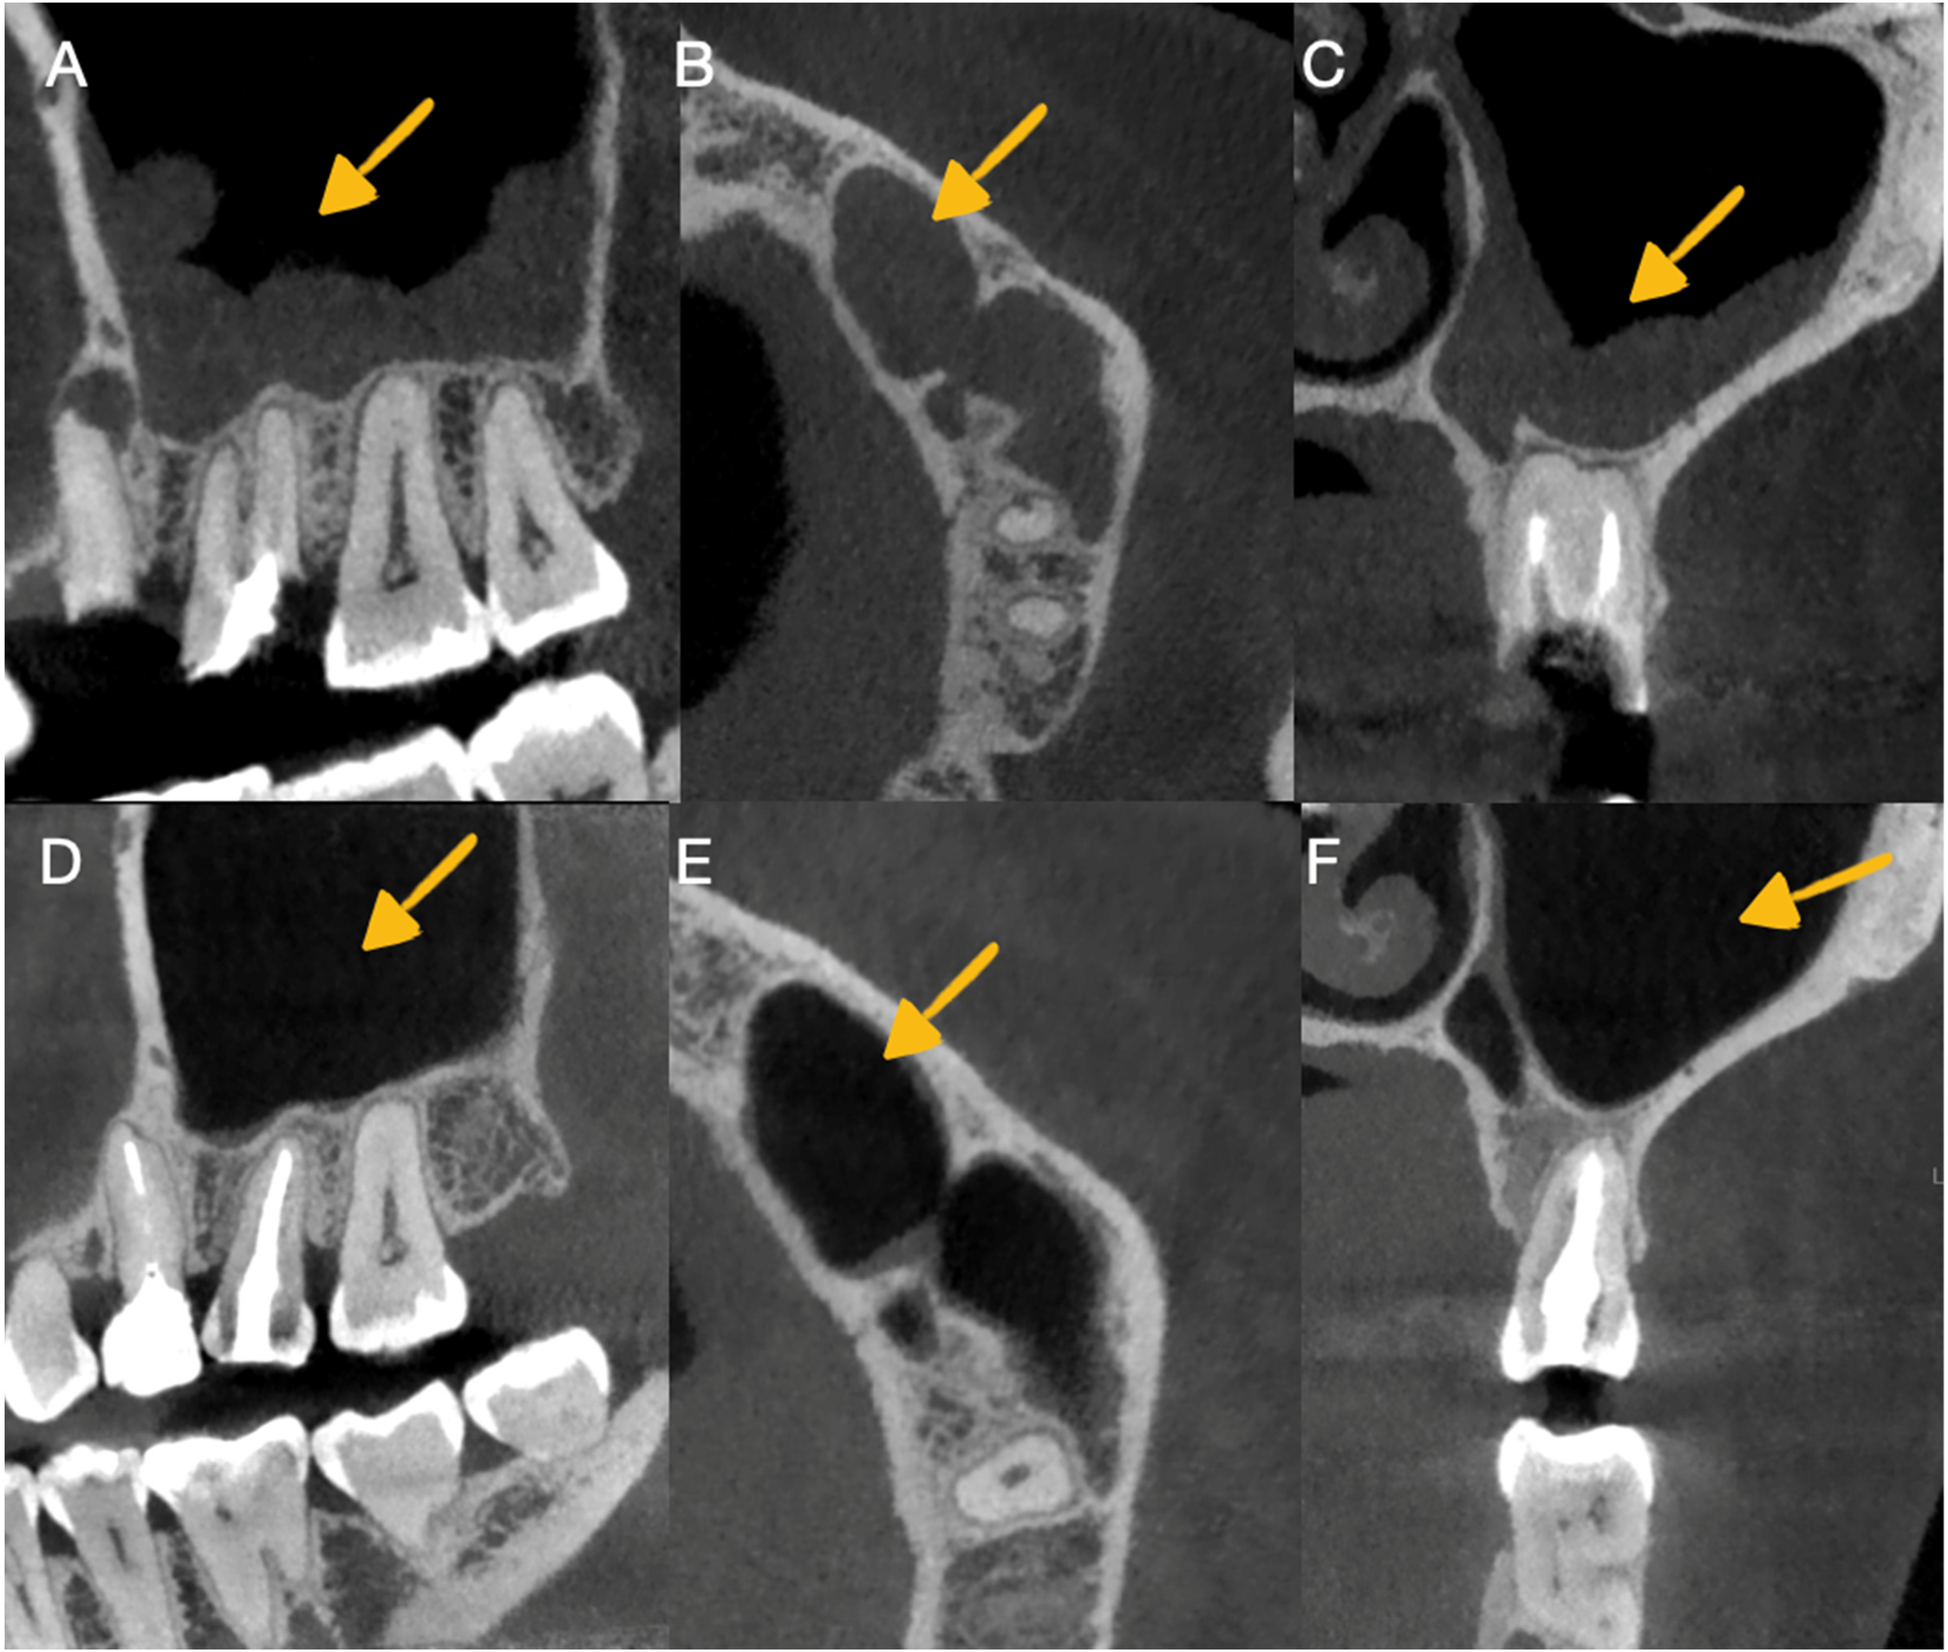

Following the guidelines of the European Society of Endodontics, cone beam computed tomography (CBCT) was performed with a small 6 cm × 6 cm field of view obtained from the tomographic equipment (GIANO HR, NewTon, Imola, Italy). The tomographic images confirmed the presence of apical periodontitis at the level of the right upper molar with subobturation of the root canal, and in the second premolar, a periapical abscess with subobturation was observed, which was associated with odontogenic sinusitis (Figures 2A–C).

Figure 2. Imaging in CBCT of odontogenic sinusitis before and after autotransplantation. (A) Observation of sinusitis in the sagittal section before retreatment and autotransplantation. (B) Observation of sinusitis in the axial section before retreatment and autotransplantation. (C) Observation of sinusitis in the transaxial section before retreatment and autotransplantation. (D) Observation of sinusitis healing in the sagittal section. Periodontal ligament continuity and alveolar bone formation were observed in the autotransplanted tooth. (E) Observation of sinusitis healing in the axial section. (F) Observation of sinusitis healing in the transaxial section and control of the periodontal ligament continuity with alveolar bone formation in the autotransplanted tooth.

The patient was monitored clinically and radiographically during the first and second years after the autotransplantation procedure (Figures 1D,E) and, in the third year, clinical (Figure 3D) and tomographic evaluations were performed, with adequate soft tissue healing and bone neoformation with continuity of the periodontal ligament at the level of the autotransplanted dental organ observed (Figures 2D–F).